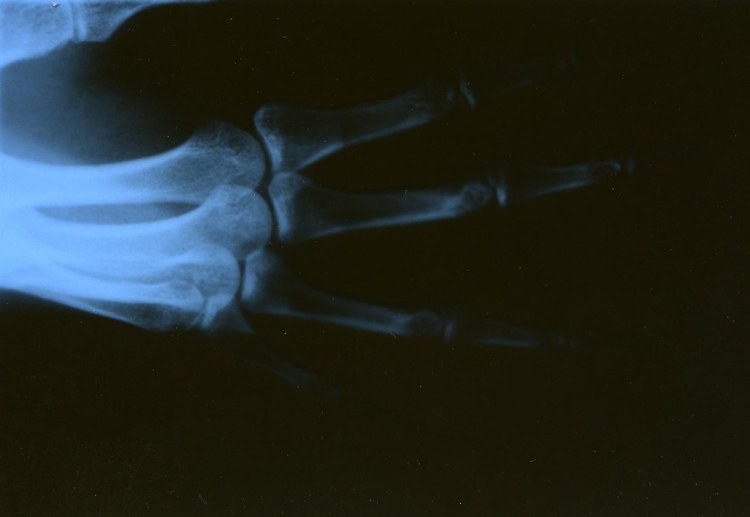

Una radiografía es una técnica médica centenaria que permite obtener una imagen del interior del cuerpo utilizando pequeñas cantidades de radiación. Una máquina de rayos X emite radiación que atraviesa el cuerpo para producir una imagen en blanco y negro de los huesos y órganos de una persona. Una vez que se hayan tomado las imágenes, aparecerán en la pantalla de un monitor o en una película para que el radiólogo las examine y luego las discuta con usted.

Rápida y sin dolor, se puede recomendar una radiografía de bebé si su especialista necesita verificar o confirmar un diagnóstico determinado. Gracias a esta tecnología, las radiografías pueden mostrar si su bebé tiene huesos rotos, un problema potencial en los dientes o la mandíbula, una enfermedad como neumonía o una afección cardíaca. Si su bebé tiene problemas para respirar, dolor en el pecho o se ha tragado un objeto, como un Lego o la tapa de un bolígrafo, una radiografía también puede ayudar a su proveedor a ver qué está pasando.

Su bebé podría tener una radiografía dental o una radiografía de tórax, según sus síntomas, o puede necesitar una radiografía durante un procedimiento en particular, como la colocación de un tubo interno o durante una operación. Pero sin importar el motivo, sepa que los proveedores de atención médica que recomiendan radiografías para bebés siguen pautas estrictas descritas.